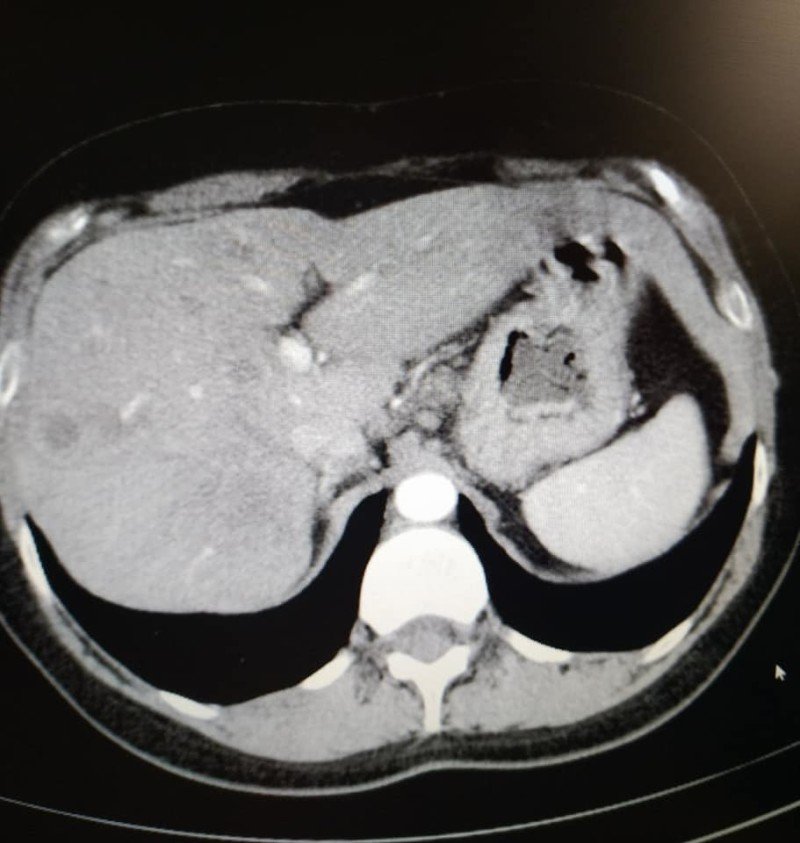

«У мене метастази, 4 стадія, але постійна від початку лікування позитивна динаміка. З 5 пухлин різних за розмірами в печінці, залишилася одна 12 на 10мм, яка була на початку 50мм. На першому фото печінки видно плями темні-це вони,метастази,а на другому фото теперішній стан. Це дуже успішне лікування. Ще трішки і я надіюсь і ця пухлина теж зникне», – розповіла вона.